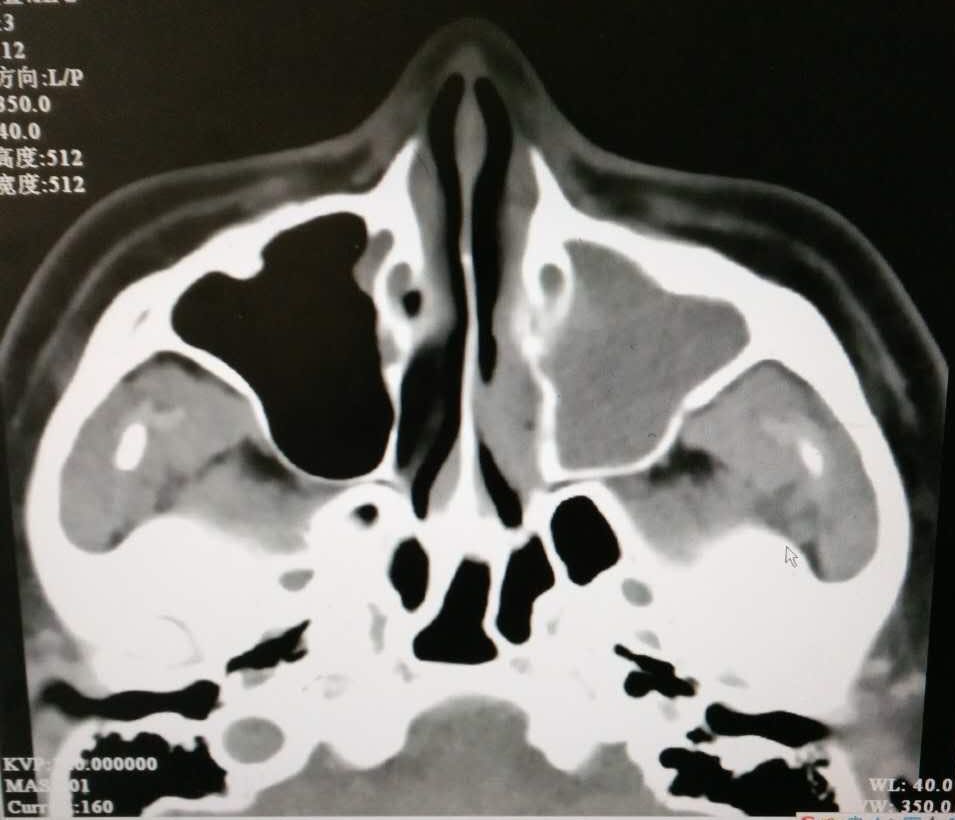

查体:鼻腔黏膜慢性充血,鼻腔内可见脓性分泌物,鼻中隔向左偏曲,双侧下鼻甲肥大。鼻内镜:双侧鼻腔可见脓性分泌物,鼻中隔左偏,进镜困难,似有中鼻道息肉,鼻咽部黏膜光滑,无新生物。鼻窦CT:双侧上颌窦、筛窦及鼻腔内炎症改变。

诊断:1.慢性鼻窦炎鼻息肉(左)2.鼻中隔偏曲 治疗:入院后完善检查,全麻下行导航鼻内镜下左侧上颌窦、筛窦开放术+鼻中隔矫正+双下甲骨折外移术。术中见左侧上颌窦内淡黄色光滑息肉样新生物,肿物根部位于底壁。